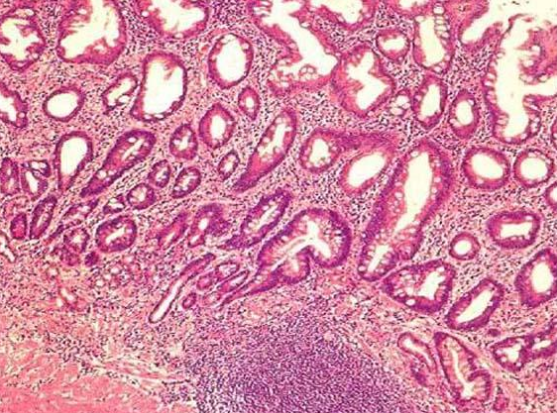

什么是萎缩、肠化?

癌前病变是癌症发生前的一些病理状态。虽然癌症都会经历癌前病变,但癌前病变不是癌症,也不一定发展成癌症,大部分会处于一种稳定状态,有的甚至会逆转到正常状态,最终有极小一部分演变成癌症。

慢性萎缩性胃炎是慢性胃炎的一种类型。简单解释,慢性萎缩性胃炎就是因为多种原因,导致胃粘膜变薄,分泌消化液的腺体减少。

慢性萎缩性胃炎在55岁人群中非常普遍,检出率大于50%。目前认为,绝大多数慢性萎缩性胃炎治疗效果比较理想,仅少数会癌变(多数研究发现癌变率不超过3%)。但有一点值得注意:一旦胃黏膜出现不典型增生,癌变机会将会明显增加。